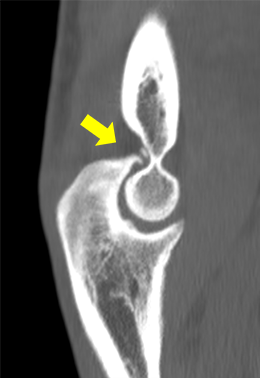

肘関節後方の骨棘と遊離体(後方インピンジメント)

野球肘の診断は問診や身体所見がとても大切です。特に、疼痛部位やどの動作で痛みが出現するかが診断・治療に重要になります。当院では、問診や身体所見に加えてまず手関節X線撮影を行い関節変形の評価を行います。X線では離断性骨軟骨炎や骨棘(こつきょく)、遊離体などが認められる場合があります。また、超音波画像やCT、MRIにより靭帯損傷や炎症など含めて、病変部をより詳細に評価します。

投球動作のフォロースルーの際、肘を伸ばしきった時に肘の後方で骨同士(上腕骨と尺骨)がぶつかり痛みが出ます(後方インピンジメント)。